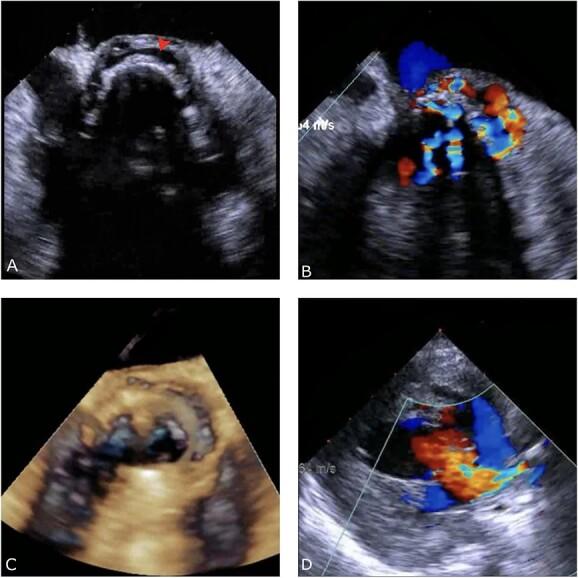

Rare but potentially fatal, brucellosis prosthetic valve endocarditis is a complication of brucellosis caused by Brucella species. The symptoms of brucellosis can be nonspecific, making the diagnosis challenging. Osteoarticular involvement is the most common complication of brucellosis. Mortality from brucellosis is low except for endocarditis and involvement of the central nervous system. The diagnosis is based on laboratory tests and clinical manifestations. Serological tests are preferred, as culture methods can be unreliable. A 59-year-old woman presented with gastrointestinal bleeding, fever, anorexia and malaise. She had a history of aortic valve replacement with a mechanical prosthesis for severe bicuspid aortic stenosis. Investigations revealed a multiloculated aortic root abscess encircling the prosthetic valve. She was diagnosed with brucella endocarditis, treated with antibiotics and underwent cardiac surgery. Her symptoms improved following the surgery. Brucellosis prosthetic valve endocarditis is a rare presentation of this disease.

摘要

布鲁氏菌性人工瓣膜心内膜炎虽罕见但可能致命,是由布鲁氏菌属引起的布鲁氏菌病的一种并发症。布鲁氏菌病的症状可能不具特异性,这使得诊断颇具挑战性。骨关节受累是布鲁氏菌病最常见的并发症。除心内膜炎和中枢神经系统受累外,布鲁氏菌病的死亡率较低。诊断基于实验室检查和临床表现。血清学检测更为可取,因为培养方法可能不可靠。一名59岁女性出现胃肠道出血、发热、厌食和全身不适。她有因严重二叶式主动脉瓣狭窄接受机械瓣膜主动脉瓣置换术的病史。检查发现围绕人工瓣膜的多房性主动脉根部脓肿。她被诊断为布鲁氏菌性心内膜炎,接受了抗生素治疗并接受了心脏手术。术后她的症状有所改善。布鲁氏菌性人工瓣膜心内膜炎是这种疾病的罕见表现。